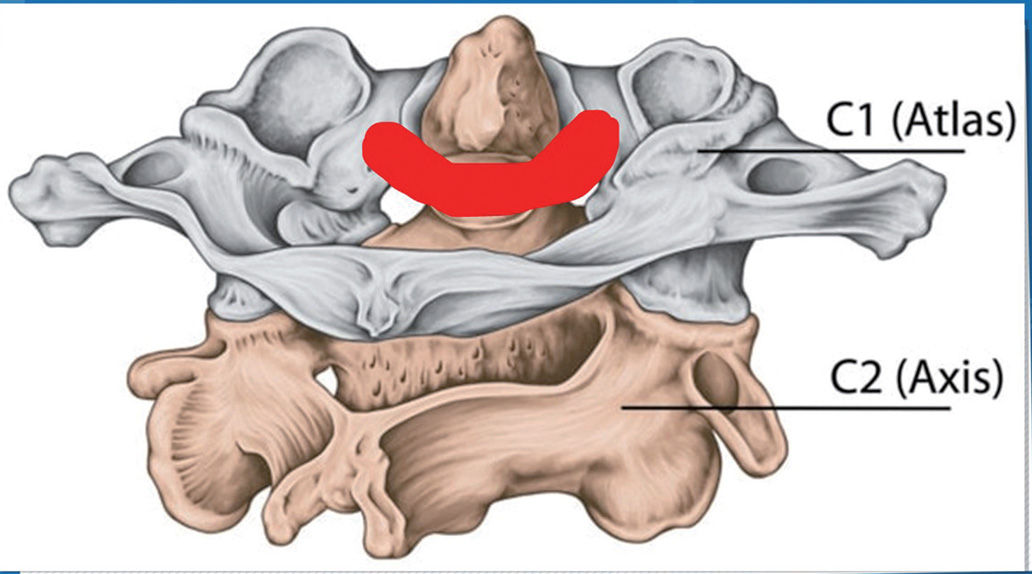

- 가동관절③ 중쇠관절